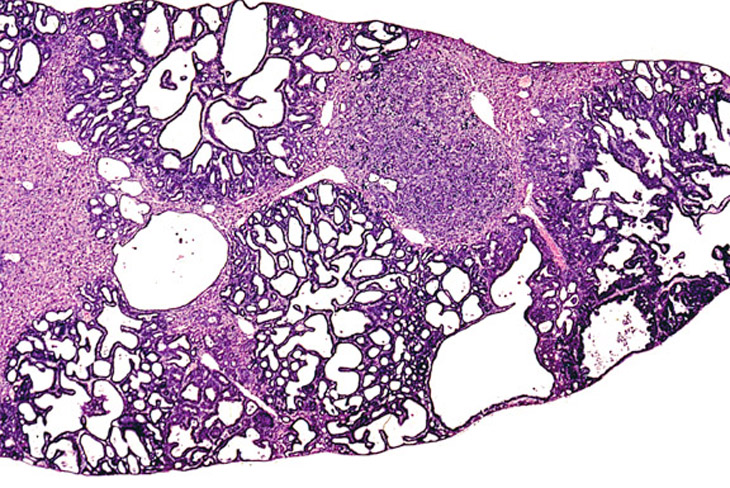

Multiple biliary and hepatocellular hyperplastic and neoplastic lesions in the liver of a 4-week-old transgenic mouse.

Confluent biliary and hepatocellular neoplasms totally occupying the left liver lobe of a 4-week-old transgenic mouse.